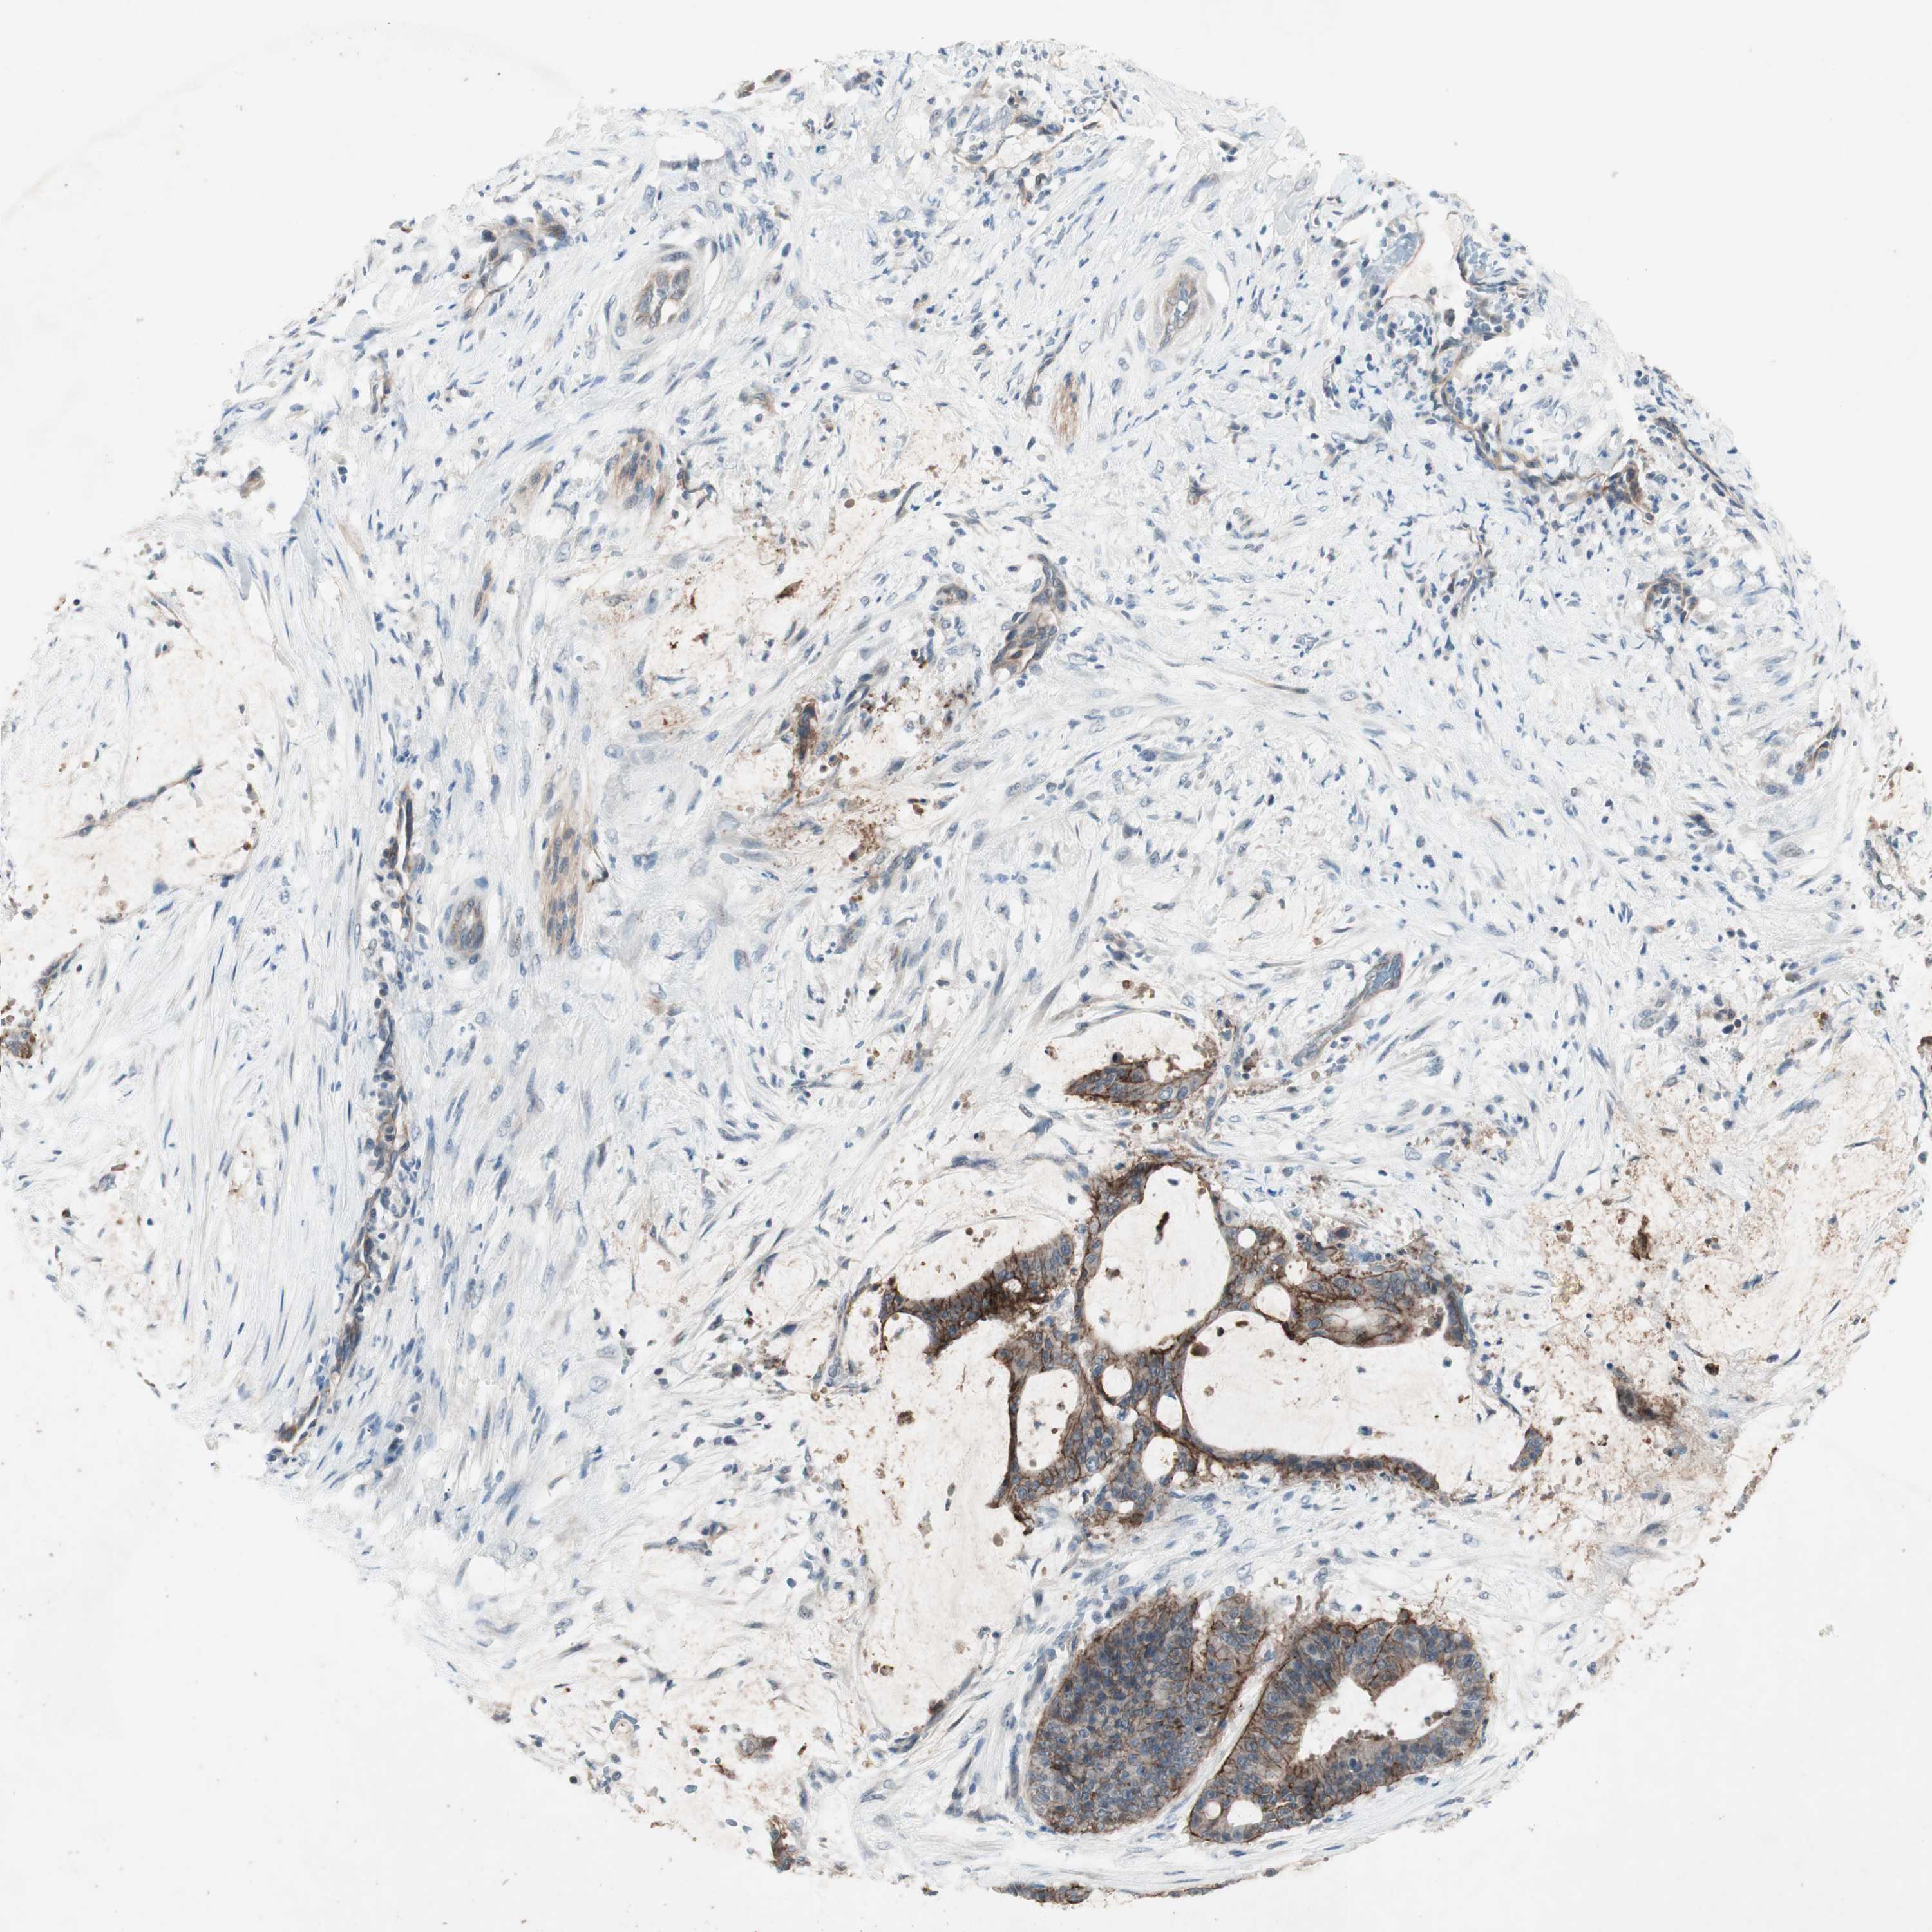

LIVER CANCER - Protein expressioni

A mouse-over function shows sample information and annotation data. Click on an image to view it in a full screen mode. Samples can be filtered based on level of antibody staining by selecting one or several of the following categories: high, medium, low and not detected. The assay and annotation is described here.

Note that samples used for immunohistochemistry by the Human Protein Atlas do not correspond to samples in the TCGA dataset.

Antibody stainingi

Antibody staining in the annotated cell types in the current human tissue is reported as not detected, low, medium, or high, based on conventional immunohistochemistry profiling in selected tissues. This score is based on the combination of the staining intensity and fraction of stained cells.

Each image is clickable and will lead to virtual microscopy that enables deeper exploration of all samples and also displays staining intensity scores, fraction scores and subcellular localization as well as patient and tissue information for each sample.

Antibody HPA036348

Antibody HPA036349

Antibody CAB002422

Antibody CAB005258

Staining

High

Medium

Low

Not detected

Intensity

Strong

Moderate

Weak

Negative

Quantity

>75%

75%-25%

<25%

None

Location

Nuclear

Cytoplasmic/membranous

Cytoplasmic/membranous,nuclear

Cholangiocarcinoma

Carcinoma, Hepatocellular, NOS